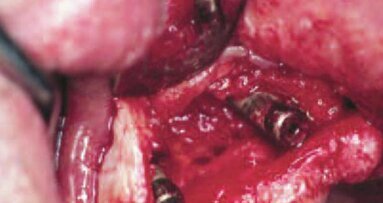

ANN ARBOR, Michigan, USA: Wraz ze wzrostem liczby wszczepianych implantów dentystycznych, rośnie także kliniczne znaczenie zrozumienia chorób około ...